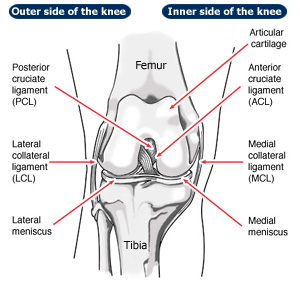

The ACL is ligament that, along with other structures, helps maintain a stable joint during the knee’s range of motion. The other main knee ligaments are: posterior cruciate ligament, medial collateral ligament and the lateral collateral ligament.

The ACL is completely within the knee joint and starts at the lateral femoral condyle of the femur (thigh bone) and attaches to the tibia (shin bone). The blood supply to the ACL is through its bony attachments and hence does not heal well.

Due to the attachments its primary responsibility is to limit forward movement of the tibia on the femur. In addition the ACL provides rotational stability to the knee during cutting activities.